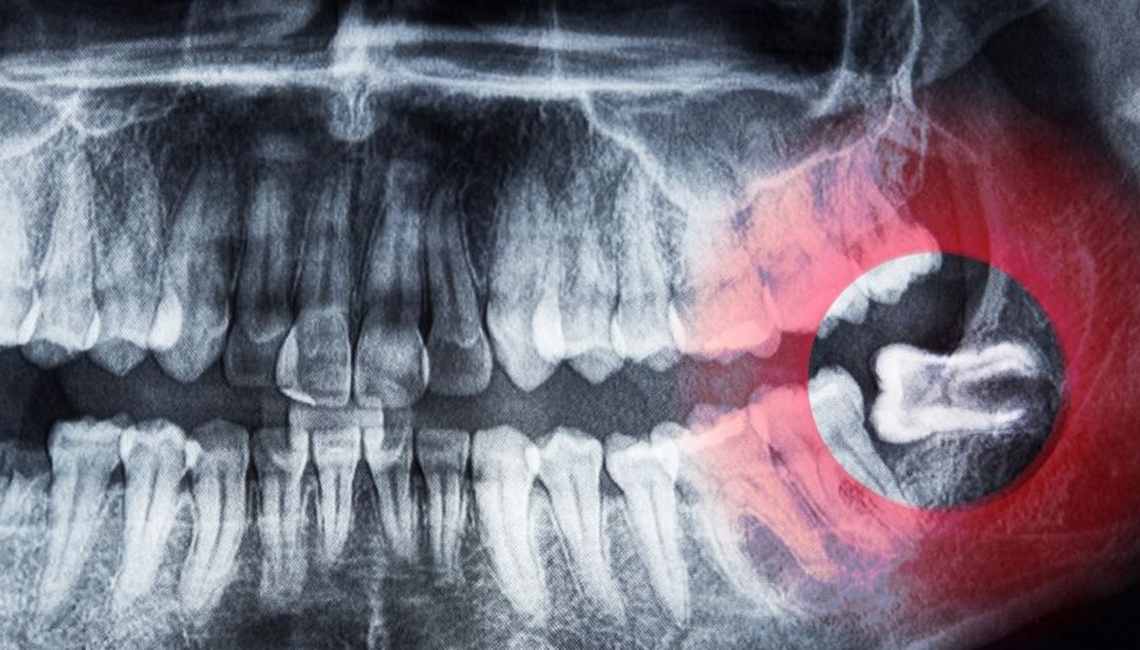

Removing eights

Eights are the teeth that give patients the most problems and inconvenience, especially when erupting in a position that prevents their complete eruption. Quite often, however, the problem is that they hardly fit in the mouth causing a lot of trouble. If the figure eight eruption has stopped and the tooth is invisible, its position is often incorrect, which can damage the roots of the remaining molars. Stopping may be painful and cause swelling. Additionally, eights are most prone to caries because access to them is difficult. This makes it much more difficult to clean them, and the food remaining in their vicinity causes the formation of bacteria.

1. At the first consultation visit, the doctor takes a pantomographic picture, thanks to which he can see the position of the tooth and the course of its roots